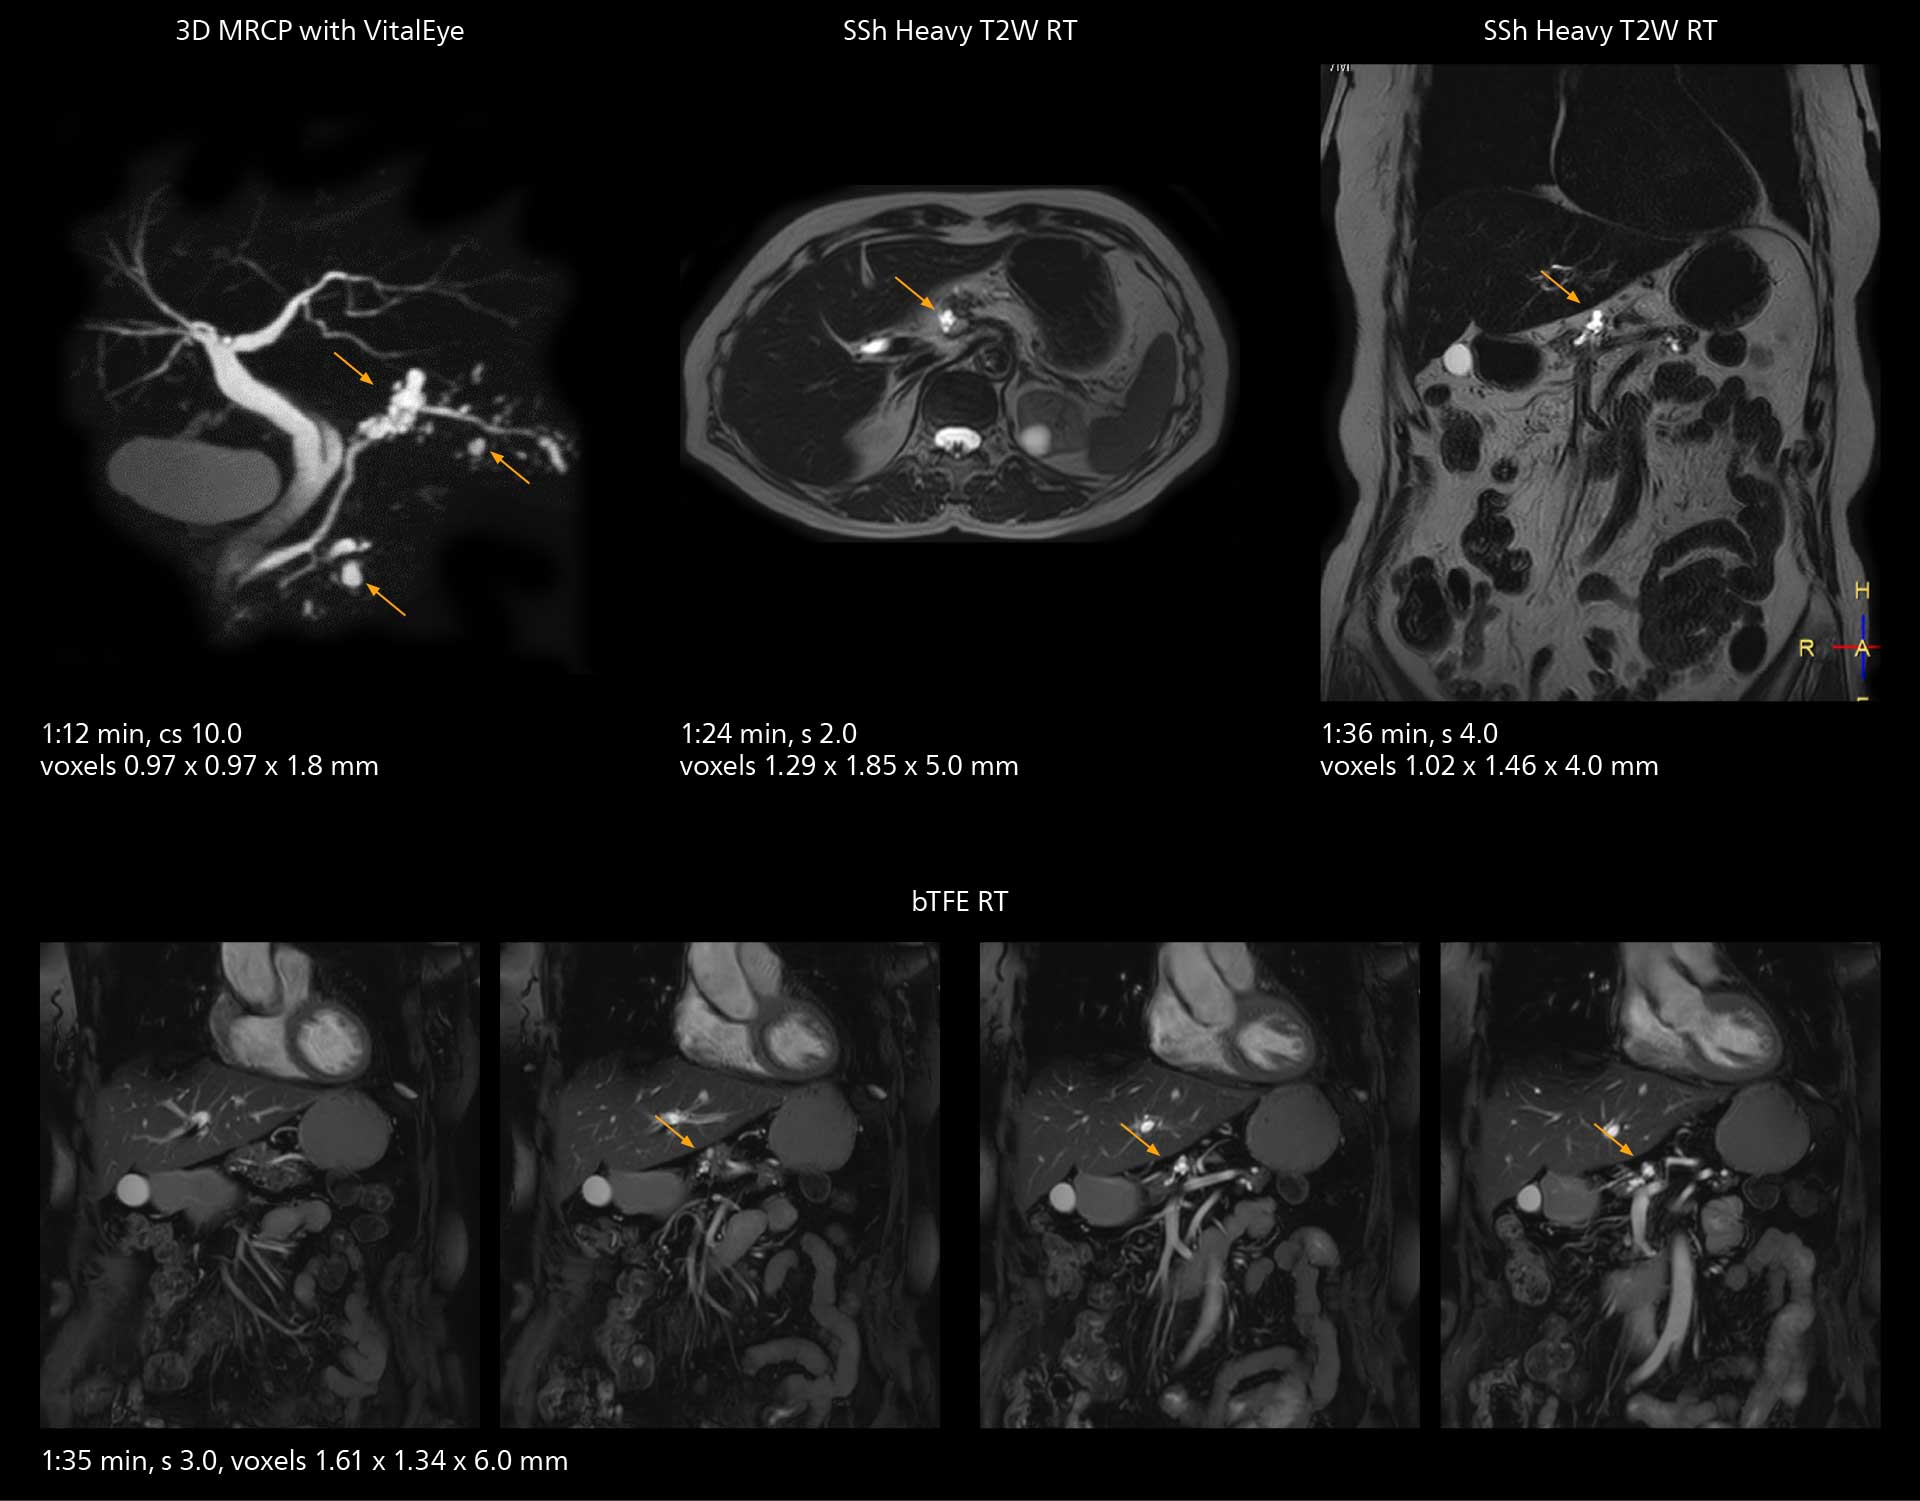

The high performance of the Vega HP gradients is particularly impressive in DWI. “The Vega HP gradients enable us to scan faster and use b-values as high as 2000, for example in prostate DWI and in DWIBS, which provides image quality that is remarkably improved over the previous system and we are able to more easily see lesions.”

Examples of prostate imaging showing faster scan times and improved resolution illustrate the power of SmartPath to Elition X in this case of prostate cancer with PI-RADS score 4.